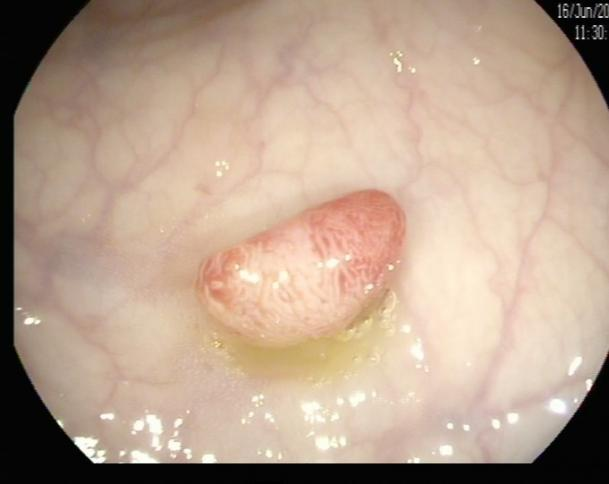

(1)赖女士(62岁,横结肠息肉,图1)

肠镜一照,息肉现形!形态各异的大肠息肉,离癌有多远?(图1)

图1

病理诊断:管状腺瘤,伴低级别上皮内瘤变。

解读:管状腺瘤是最常见的腺瘤性息肉。低级别上皮内瘤变意味着腺体结构和细胞出现了轻度到中度的异常改变,是明确的癌前状态。此阶段积极切除并定期复查,可有效阻断癌变进程。距离癌:一步之遥,癌前病变中期。